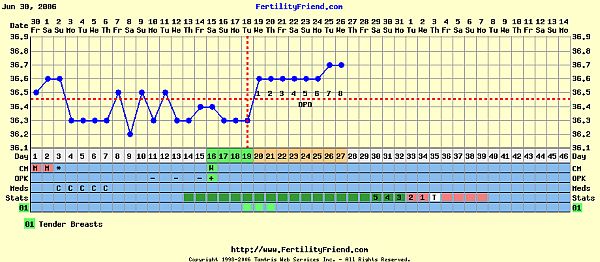

Köszönöm, hogy megnéztétek, és véleményeztétek a görbémet, ami…. Hát szóval ebben a hónapban nem éppen görbe formájú!

Sajna nem nagyon ment feljebb a hőm. Ez van.

Kicsit lehangolt, hogy most volt először + az LH teszt, és akkor épp most nincs peteérésem…:evil:

Sőt! Most égetem magam egy kicsit, de én a napokban világosodtam meg, hogy ez az LH teszt nem is azt mutatja, hogy mikor van peteérésem, csak a peteéréshez szükséges hormonális környezet meglétét, de cseppet sem biztos, hogy peteérés is követi!

Hát nekem most nem követte!